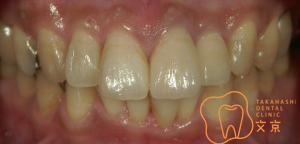

■前歯を治したい。 オールセラミックスによる審美治療

■前歯を治したい。40代男性 オールセラミックスによる審美治療

■前歯を治したい 精密審美治療・セラミックス治療

■前歯 精密審美治療

■前歯のセラミックス治療 審美治療

■前歯のオールセラミックス治療

■保険の前歯を直したい